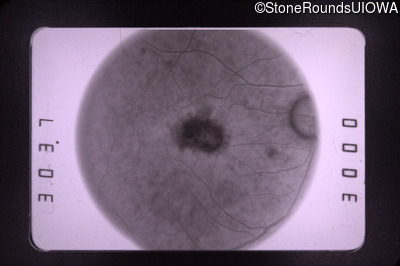

Fluorescein Angiography - Left - 20/40 +3

Exemplar